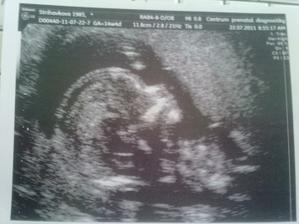

12.9.11 Emis je dle utz zcela zdrava, azi 440g, meri po prdelku 20cm, takze celkem cca 27cm, dalsi KO 10.10., predtim jeste absolvovat test na cukrovku.